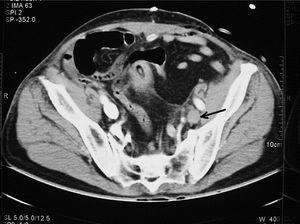

Varón de 62 años con antecedentes médicos de hipertensión arterial, resección transuretral de próstata hace 2 meses e infecciones urinarias de repetición tratadas con ciprofloxacino. Es intervenido de forma programada de adenocarcinoma de próstata, realizando resección prostática radical ampliada. Al cuarto día de postoperatorio presenta hipotensión arterial, oliguria, alteraciones de la coagulación compatibles con coagulación intravascular diseminada, y brusca disminución del hematocrito y de la hemoglobina (24% y 7,5 g/dl respectivamente). Es ingresado en la Unidad de Cuidados Intensivos (UCI) precisando perfusión de noradrenalina, trasfusión de 3 concentrados de hematíes, plaquetas y plasma fresco congelado, siendo intubado a las pocas horas de su ingreso tras disnea brusca. Se realizó tomografía axial computarizada toraco-abdominal de urgencia apreciando restos sanguíneos en vejiga y trombosis de eje esplenoportal y de vena ilíaca primitiva izquierda (figs. 1 y 2). Se implantó filtro en la vena cava inferior, una vez corregidas las alteraciones de la coagulación.

Figura 1

Figura 2